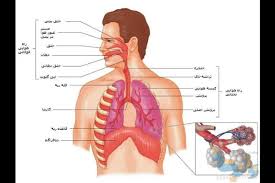

قیمت: 68٬000 تومان - دسته بندی فایل: تحقیقپاورپوینت آناتومی و فیزیولوژی دستگاه تنفس (ppt) 42 اسلاید

فروش ویژه فایل های پاورپوینت آناتومی و فیزیولوژی دستگاه تنفس با تخفیف استثنایی - دسته بندی: پاورپوینت نوع فایل: PowerPoint (pptx) (قابل ویرایش و آماده پرینت) تعداد اسلاید: 42 اسلاید

قیمت: 10٬000 تومان - دسته بندی فایل: تحقیقپاورپوینت آمبولی ریه (ppt) 9 اسلاید

فروش ویژه پاورپوینت حرفه ای آمبولی ریه با تخفیف استثنایی فقط 10 هزار تومان